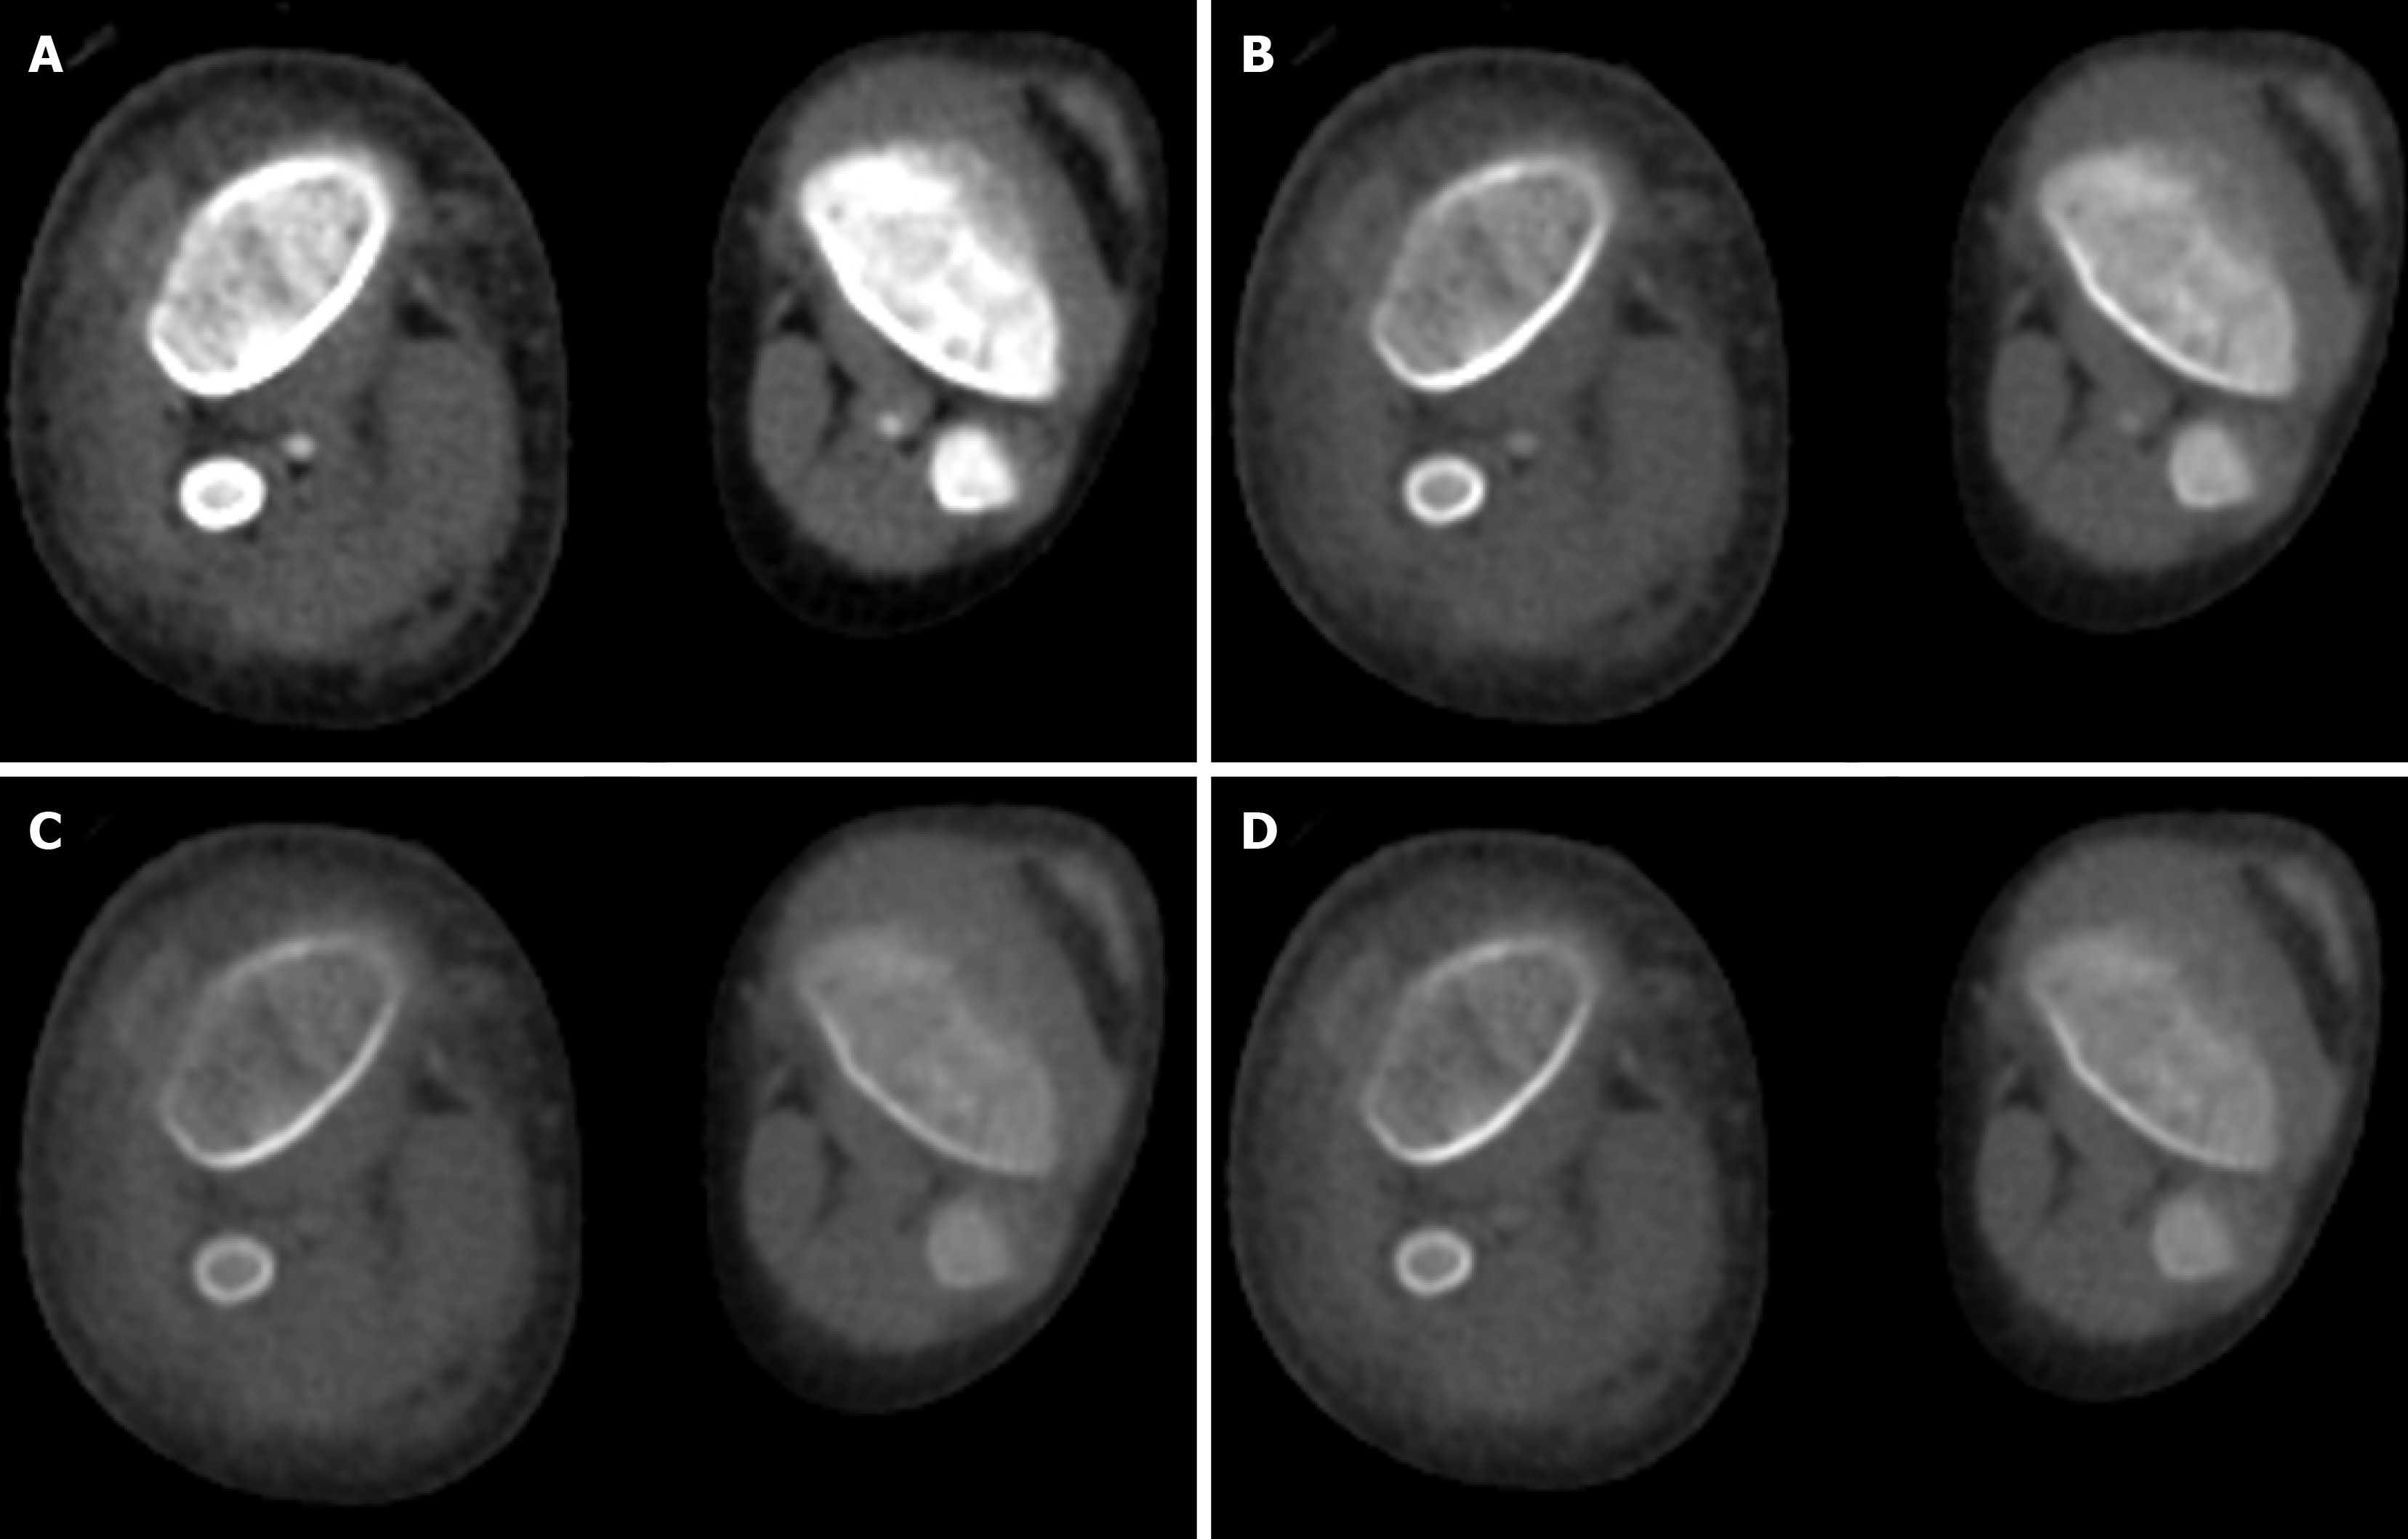

Figure 4 A 4-year-old male with trauma.

Axial virtual monoenergetic images of CT angiography of the bilateral lower limb vessels showed popliteal arteries. A: 40 kV; B: 80 kV; C: 120 kV; D: 160 kV. There was increased conspicuity of the vessels at low kV as compared with high kV. This application allows for the generation of acceptable image quality even with a suboptimal dose of contrast.